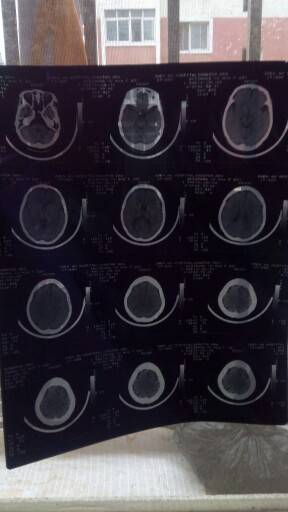

妈妈肺部和脑部肿瘤消失了